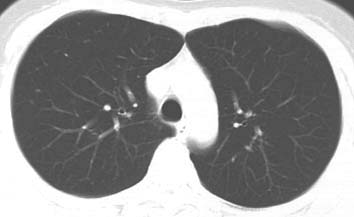

*胸部レントゲンではほとんど変化が見られない段階でもCT検査で肺胞構造が破壊されている所見を認めます。肺ドックではヘリカルCT検査を行い、肺癌を小さなうちに発見するとともに、肺気腫病変の早期発見をめざしています。喫煙指数(1日の喫煙本数×喫煙年数)が600を超える人は是非肺ドックを受けてみて下さい。

(写真は香川県立がん検診センター呼吸器科の症例)

佐藤功先生 提供

正常肺のCT 正常肺のCT

中等度肺気腫のCT 中等度肺気腫のCT

58才男性。25本/日×38年、喫煙指数950 直径1cmまでの低吸収域が集合し癒合しており、結果的にのう胞様の隔壁構造も認められる。